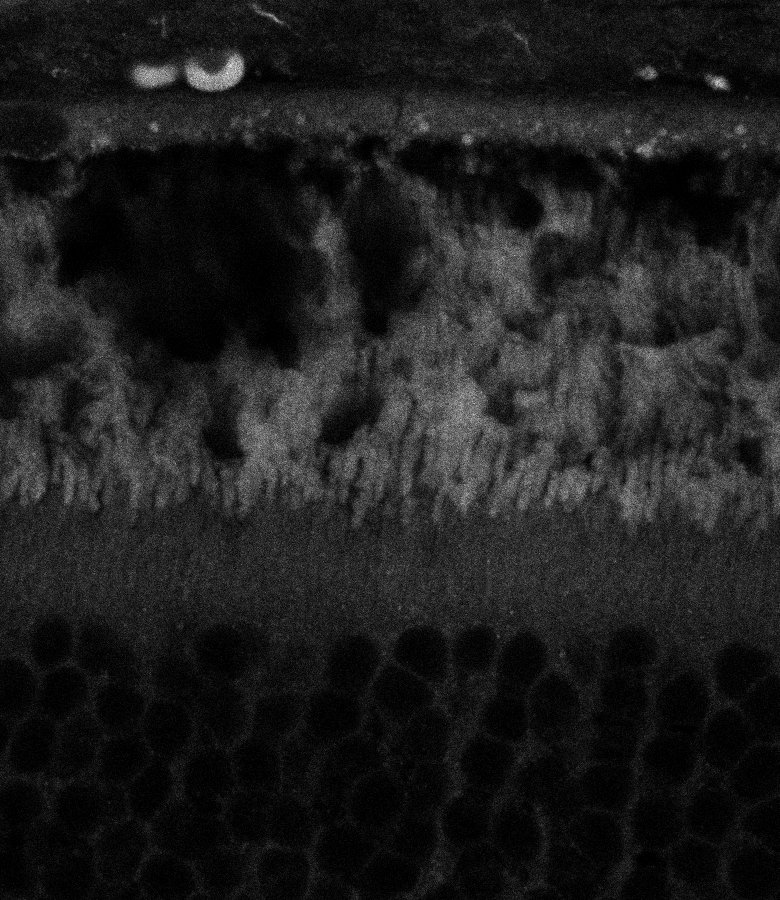

Healthy Retina

Unhealthy Retina

Healthy Choroid

Unhealthy Choroid